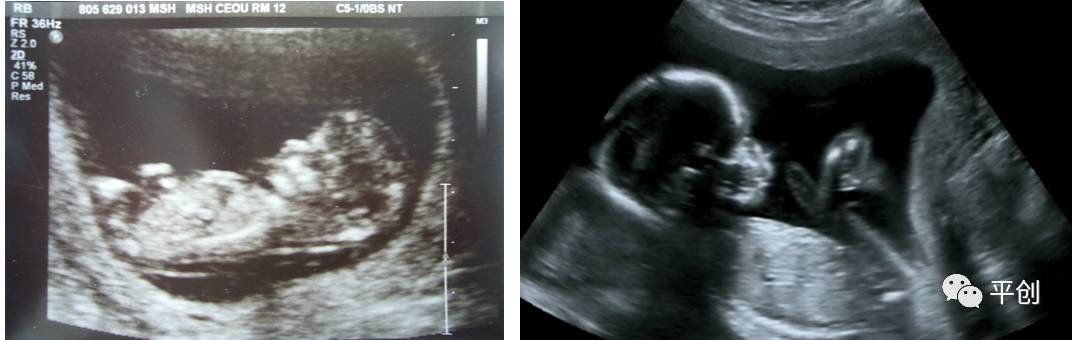

更準確的醫學診斷,來自B超檢查結果的輔助,準確的B超檢查結果,來自B超醫生看到的B超圖像,清晰的B超成像,來自好的耦合劑。所以說,好的耦合劑對B超的成像很重要。

而影響B超檢查成像的因素有兩點,一是來自好的探頭,二是來自優質的耦合劑。如果這兩個產品其中有一個質量不過關,即對B超成像有一定程度的影響,可能會有成像不清楚,醫生無法準確判斷所檢查器官的實際病變,嚴重的有可能度至醫生誤診的后果。

所生產出來的耦合劑無雜質、透明度高、不易干,不化水,易偶合、易擦凈,透聲性超過國家標準的50%(數據通過國家指定的第三方檢測機構檢測結果所得),完全地解決了成像不清晰的難題。

安創安必潔耦合劑已經在廣東省人民醫院、南方醫院、中山大學附屬第一醫院等全國各三甲醫院使用,并得到了各醫院的一致認可,解決了其它品牌耦合劑的偶合性差、透聲功能低,成像不清晰的問題,減少了B超結果誤診的機率,同時也解決了短期內要多次尋找耦合劑品牌的煩惱,所以得到了各合作醫院的聯合推薦使用:“好的耦合劑,選用安創安必潔消毒耦合劑。